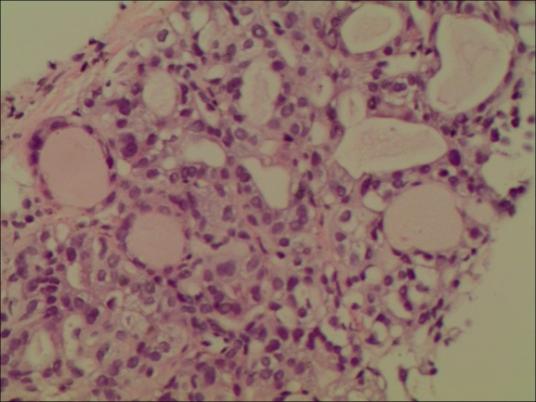

但是,由于B超的分辨率及病灶与组织密度基本一致情况下就不能做出明确诊断。因此,需要更加进一步检查。大家知道,病理学诊断是医学的最后诊断,也是医学诊断的“金标准”,那么怎样才能获得病变的组织或细胞呢?就是在B超实时引导和监视下通过一根很细针插入病灶内,获取病灶内的组织或细胞,进行病理检查,明确性质。

前面说到的甲状腺炎性及功能异常,需要内分泌医生用药物进行治疗,而结节样或肿瘤的,需要B超引导穿刺活检,明确良恶性才能选择治疗,1、良性结节可采取:手术、化学消融(结节内注射硬化剂使其坏死)和热消融(微波、射频、激光等,通过热能量使病灶坏死)。2、恶性结节,一般主张手术切除,但甲状腺乳头状癌可应用热消融技术达到治疗目的。